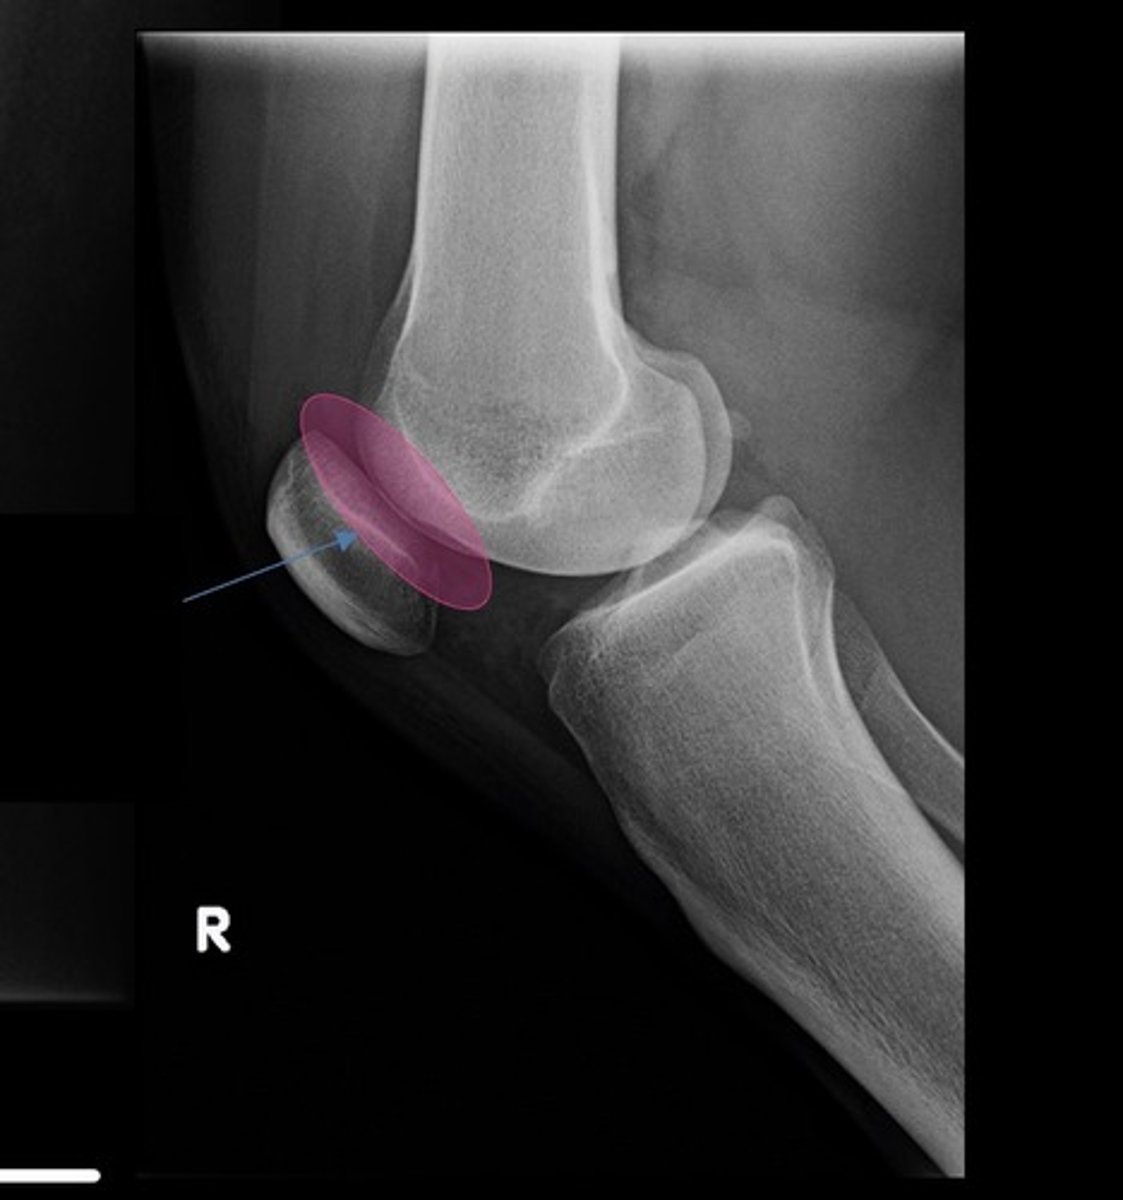

hoffa's fat pad (infrapatellar)

blumensaats line

suprapatellar bursa aka pouch